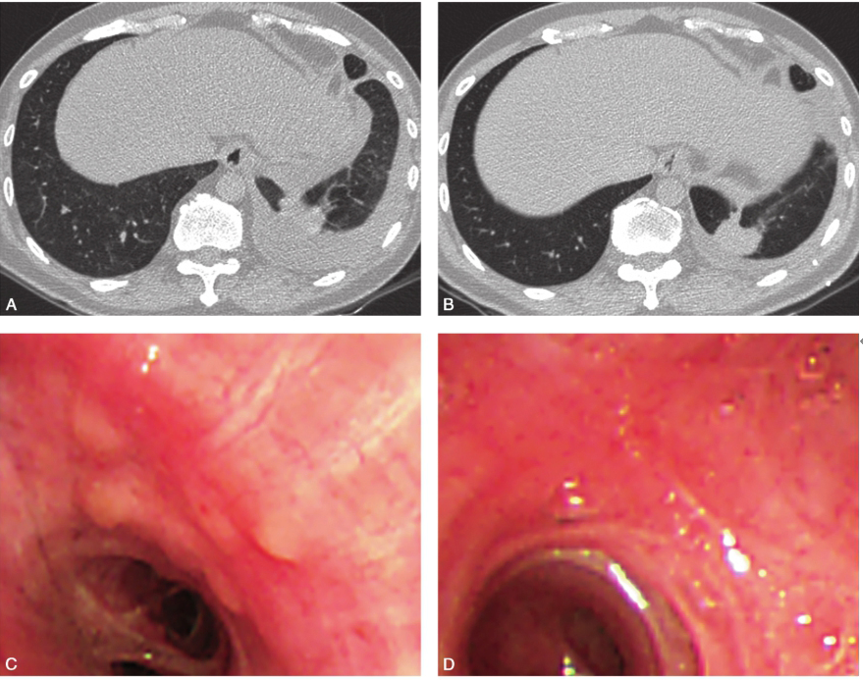

现有研究表明结节病是以Th1细胞免疫过度激活和巨噬细胞增殖为主的免疫失衡,鉴于结节病本身存在T淋巴细胞免疫功能缺陷,长期接受糖皮质激素或免疫抑制剂治疗可诱发感染等多种严重不良反应。故治疗过程中应警惕细菌、病毒、结核或真菌感染,定期复查胸部薄层CT,加强随访,早发现、早诊断、早治疗可能继发的肺部感染。患者出院后继续口服甲泼尼龙片和硫唑嘌呤治疗3个月后复查胸部CT(2017-08-03)示双侧肺野弥漫性细小结节影显著减少,胸腔积液较前显著减少。复查电子支气管镜示气道黏膜多发结节样隆起消失(图3)。

图3患者口服甲泼尼龙片和硫唑嘌呤治疗3个月后复查胸部CT:胸腔积液较前(A,2017-04-28)显著减少,双侧肺野弥漫性细小结节影显著减少(B,2017-08-03);复查支气管镜检查示原有左下叶开口处结节样隆起(C)治疗后消失(D)